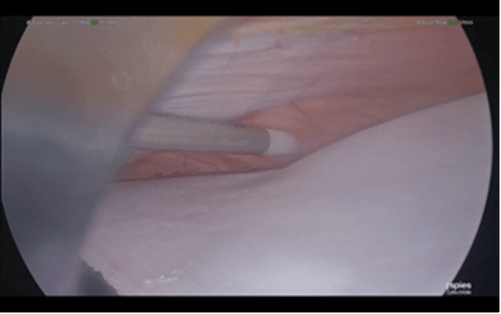

4 months later, laparoscopic left lumbar incisional hernia repair with biological mesh was carried out under general anaesthesia. A left lumbar defect which measured 18cm x 6cm was identified. The defect was closed with ten Ethibond® No 5 (Ethicon) interrupted trans fascial sutures. A laparoscopic IPOM repair was carried out using a 1.0mm thickness, 20cm x 16cm mesh formed from bovine dermal collagen matrix (Surgimend® [Integra]) which was fixed with Prolene® (Ethicon) 2/0 stays medially, laterally, and centrally. Cyanoacrylate glue (Liquiband Fix8® [Advanced Medical Solutions plc]) was used for mesh fixation to over the iliac crest, costal margin, centrally (to obliterate the dead space between mesh and peritoneum) and all other edges (Figures 2-4). There were no complications intra-operatively. Post-operatively, the patient was settled on the ward with thoracic epidural analgesia for 4 days and was discharged home 5 days after the operation.

Figure 2: Laparoscopic IPOM repair – the biologic mesh is fixed to the costal margin using cyanoacrylate glue.

Figure 3: Laparoscopic IPOM repair – the biologic mesh is fixed centrally using cyanoacrylate glue to obliterate the dead space between mesh and peritoneum.

Figure 4: Laparoscopic IPOM repair – the biologic mesh is fixed to the iliac crest using cyanoacrylate glue.